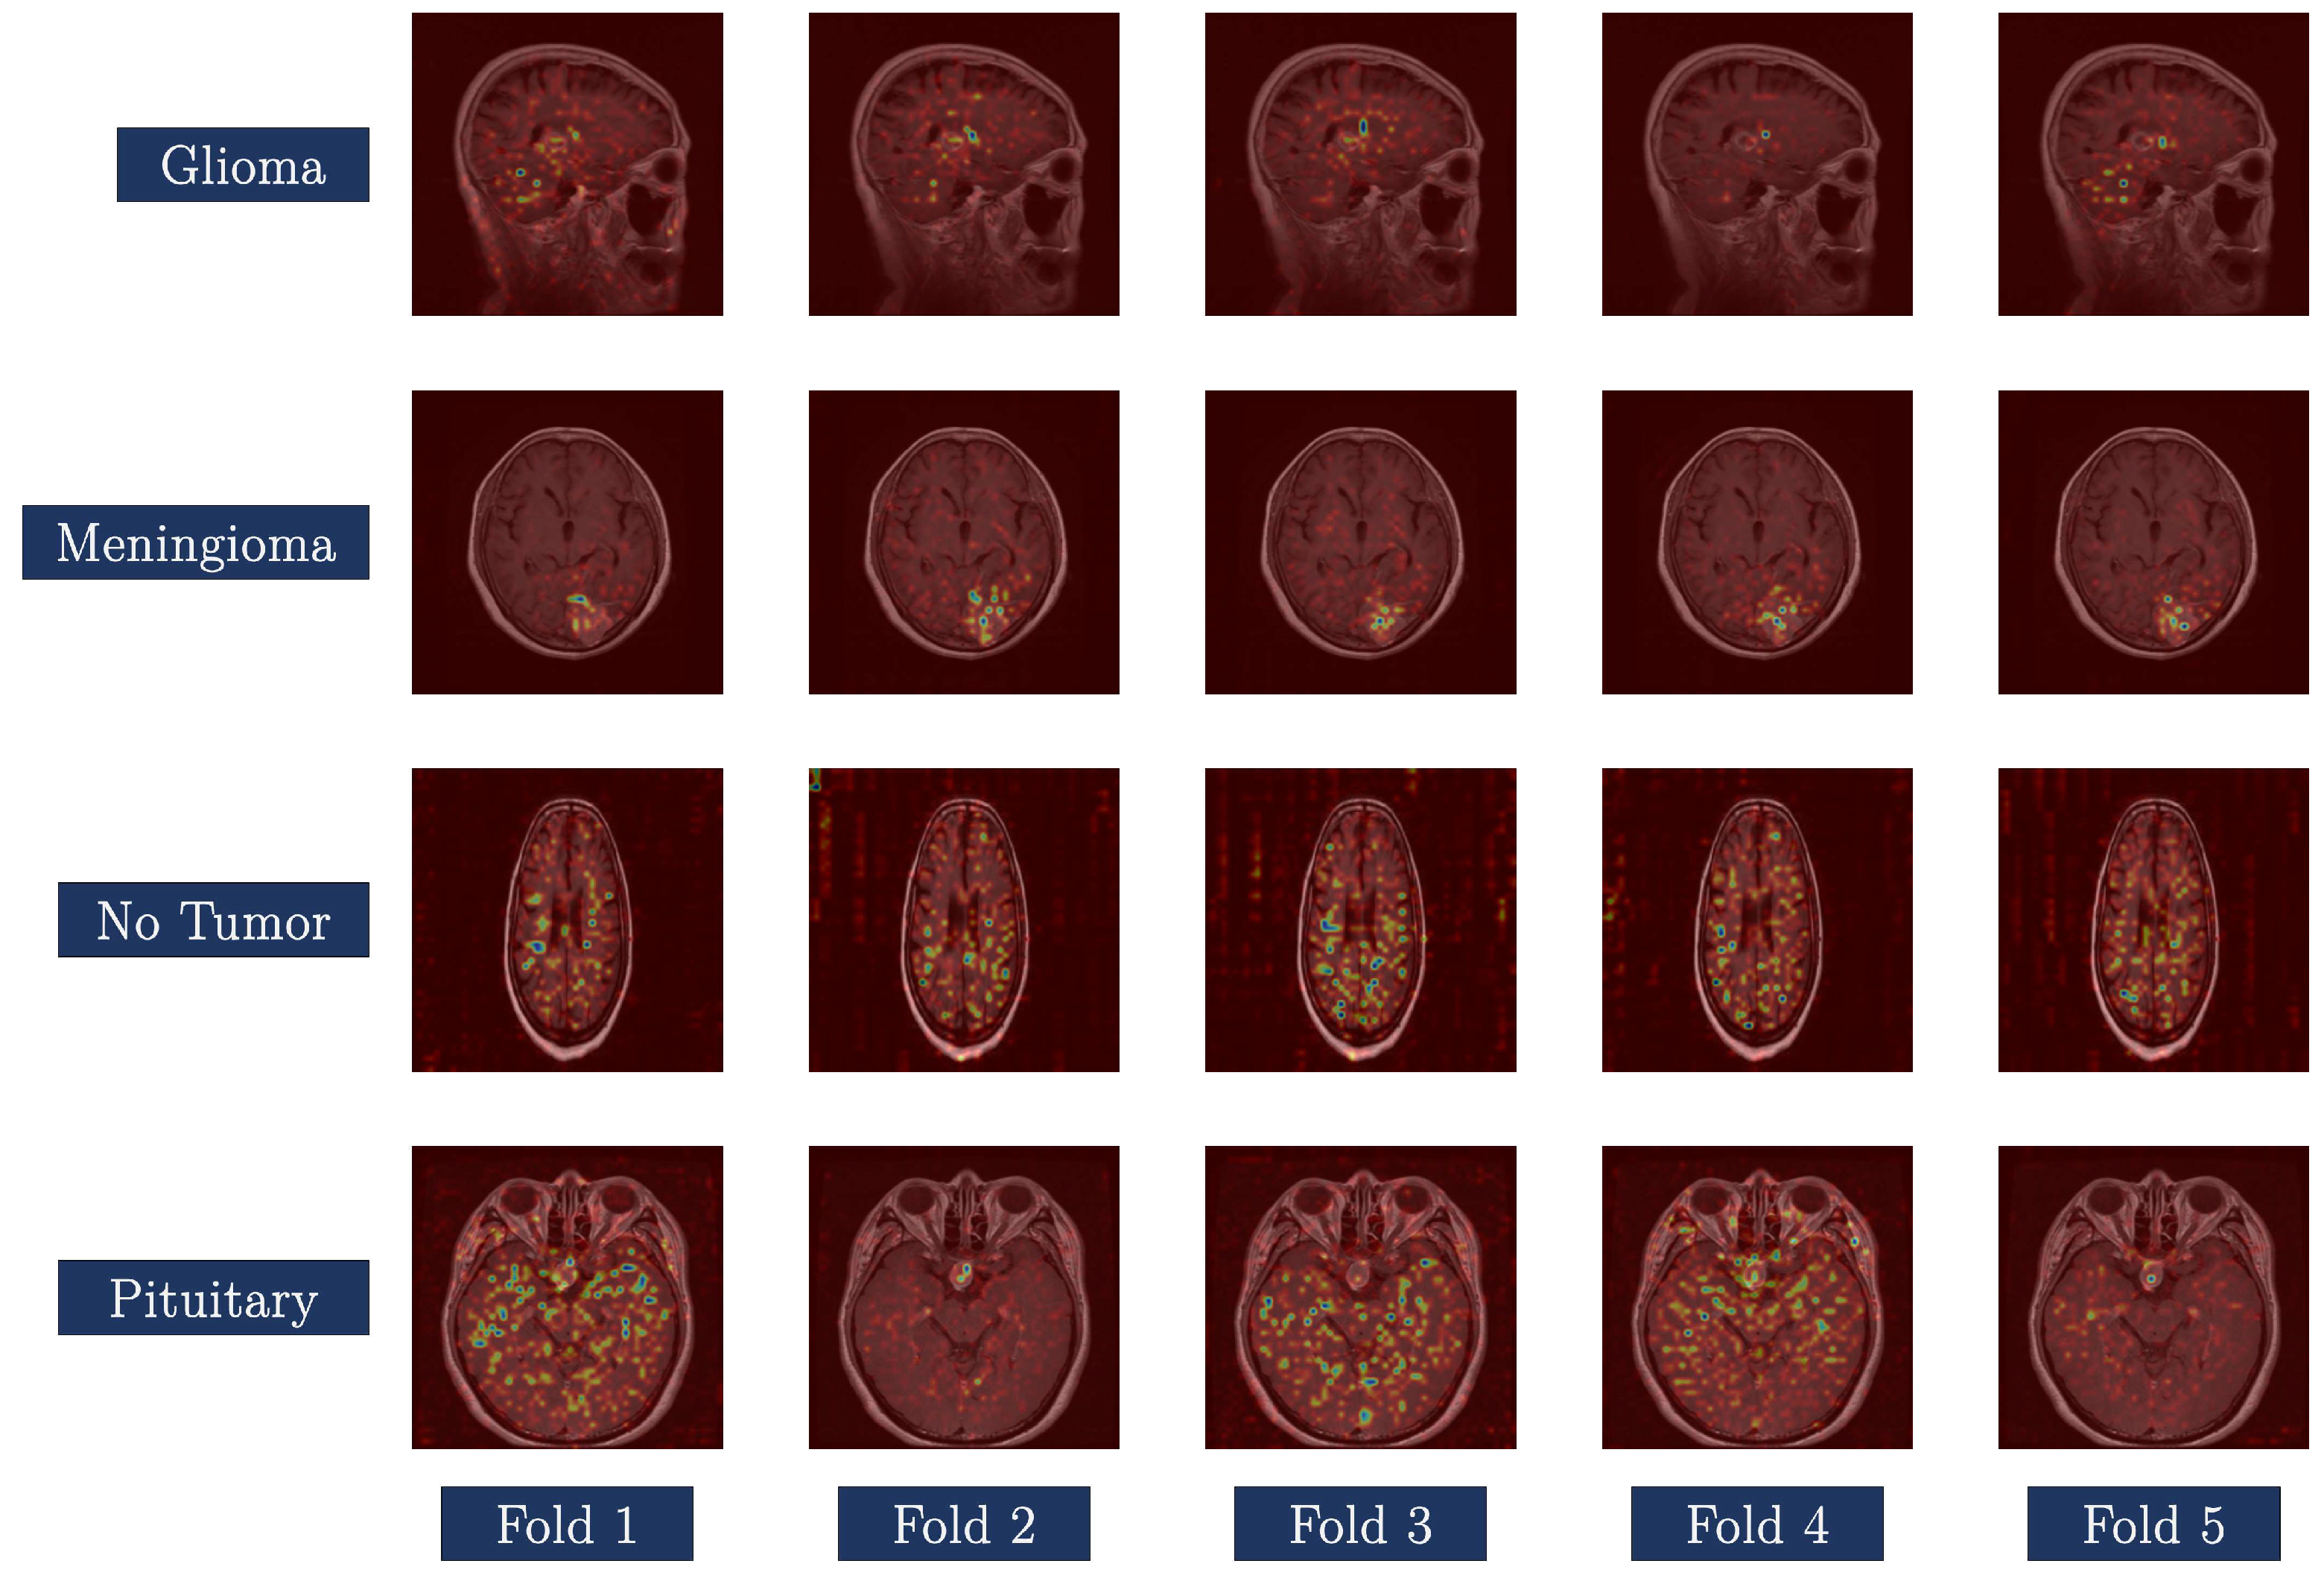

Examining the interpretability of DL models is crucial, particularly in the medical domain, where model transparency is paramount. This extends beyond examining only quantitative performance metrics, such as confusion matrices and ROC curves. Gradient-weighted Class Activation Mapping (Grad-CAM) was used to illustrate the spatial regions that significantly influenced the classification decisions of the Swin_tiny_patch4_window7_224 model. The activation maps generated from this offer a good understanding of the algorithm’s decision-making process.

Figure 13 presents Grad-CAM visualizations for test samples representative of all five folds across the four classes: glioma, meningioma, no tumor, and pituitary tumor. The class activation maps are superimposed on the MRI slices to illustrate the regions utilized by the Swin Transformer model to differentiate between classes.

Each column shows a different fold, and each row shows a different category. The pictures show that the folds are very uniform in space, which suggests that the model parameters are based on stable and anatomically relevant areas. In cases of malignant tumors (glioma, meningioma, and pituitary tumors), the highlighted areas correspond to pathological structures. This indicates that the model can identify physiologically essential features. In the glioma and meningioma groups, activations primarily occur in the areas surrounding the lesions. When it comes to pituitary tumors, the sellar area is the most important.

In the “no tumor” class, the Grad-CAMs exhibit dispersed yet low-intensity activations, indicating the absence of concentrated anomalies. This behavior aligns with the model’s accurate classification based on overarching anatomical traits. This interpretability research enhances the clinical validity of the Swin Transformer model by graphically demonstrating its decision-making process. The model achieves superior predictive Accuracy while maintaining transparency through the use of Grad-CAM. This is crucial for practical medical applications and for doctors to have confidence in the model.